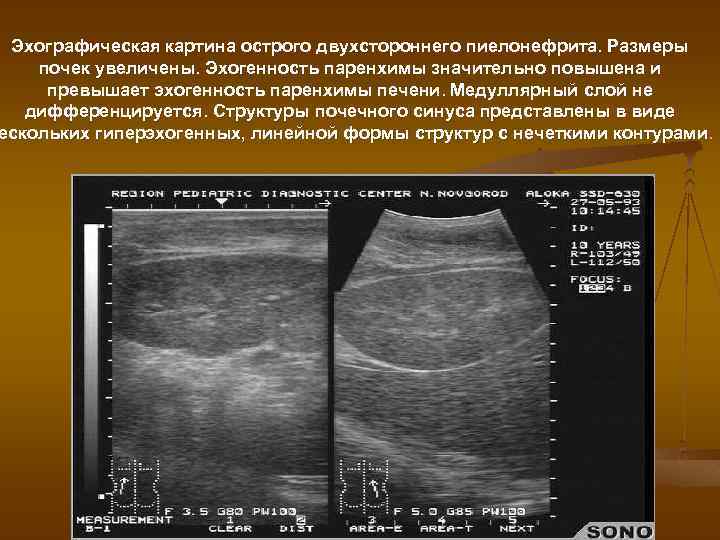

Эхографическая картина острого двухстороннего пиелонефрита. Размеры почек увеличены. Эхогенность паренхимы значительно повышена и превышает эхогенность паренхимы печени. Медуллярный слой не дифференцируется. Структуры почечного синуса представлены в виде ескольких гиперэхогенных, линейной формы структур с нечеткими контурами.